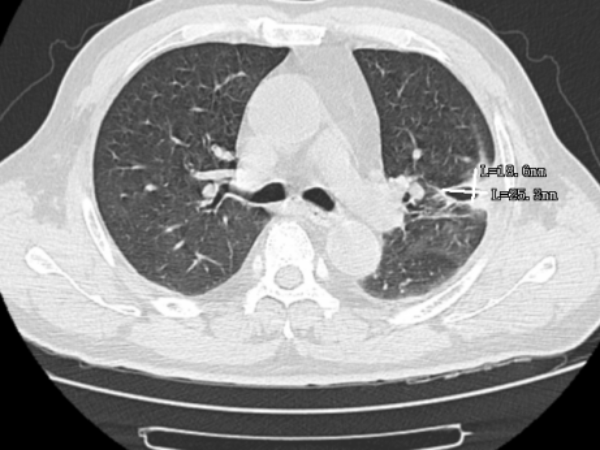

近日,博羅一位60歲的袁先生因發(fā)燒、胸痛、咳嗽且持續(xù)一周之久,到惠州市中心人民醫(yī)院博羅分院(博羅縣人民醫(yī)院)呼吸與危重癥醫(yī)學(xué)科門診就診,醫(yī)生給患者開了一個(gè)CT檢查,檢查結(jié)果出來后,發(fā)現(xiàn)患者的肺部出現(xiàn)了一個(gè)6cm的病灶,因?yàn)榛颊叱掷m(xù)發(fā)燒且溫度不降,醫(yī)生用藥后效果不明顯,于是給患者做了進(jìn)一步的氣管鏡和病原體靶向測序的檢查。

通過氣管鏡檢查,發(fā)現(xiàn)患者的肺部中有許多膿痰,氣管鏡協(xié)助將膿痰吸引干凈,并將膿痰送檢病原體靶向測序,發(fā)現(xiàn)患者存在兩種鏈球菌的感染,最終醫(yī)生根據(jù)病原體靶向測序的結(jié)果進(jìn)行針對性用藥,患者便好轉(zhuǎn)了很多,后續(xù)的CT檢查中可以看到,6cm的病灶已縮小到2cm不到。

▲治療前